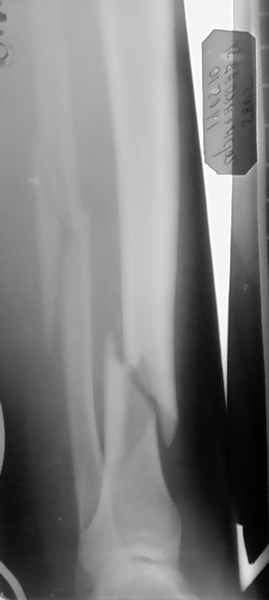

Ув. колеги, в представленном на снимках случае, возможно выполнить проведение

блокируемого стержня без аппарата ЭОП ?Заранее благодарен за отзывы и коментарии !!!!